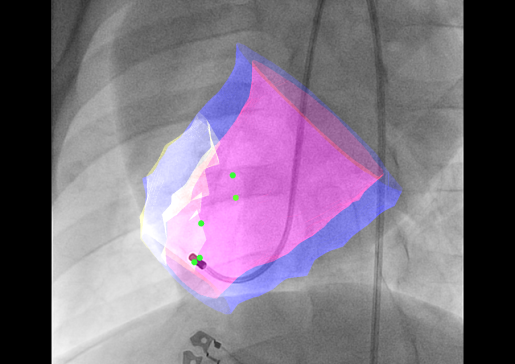

image of 3D image fusion model for transendocardial injections

Developing an Interventional Imaging Platform to Accurately Deliver Therapeutic Agents Into the Infarct and Infarct Border Zone

Transendocardial injection, in which a steerable, needle-tipped catheter is steered within the ventricle to administer therapies to target areas, is far more appealing, but his approach requires robust image guidance.

The Raval lab is developing multi-modality 3D image fusion approaches to provide accurate roadmap images of the heart for accurate and safe transendocardial injections.